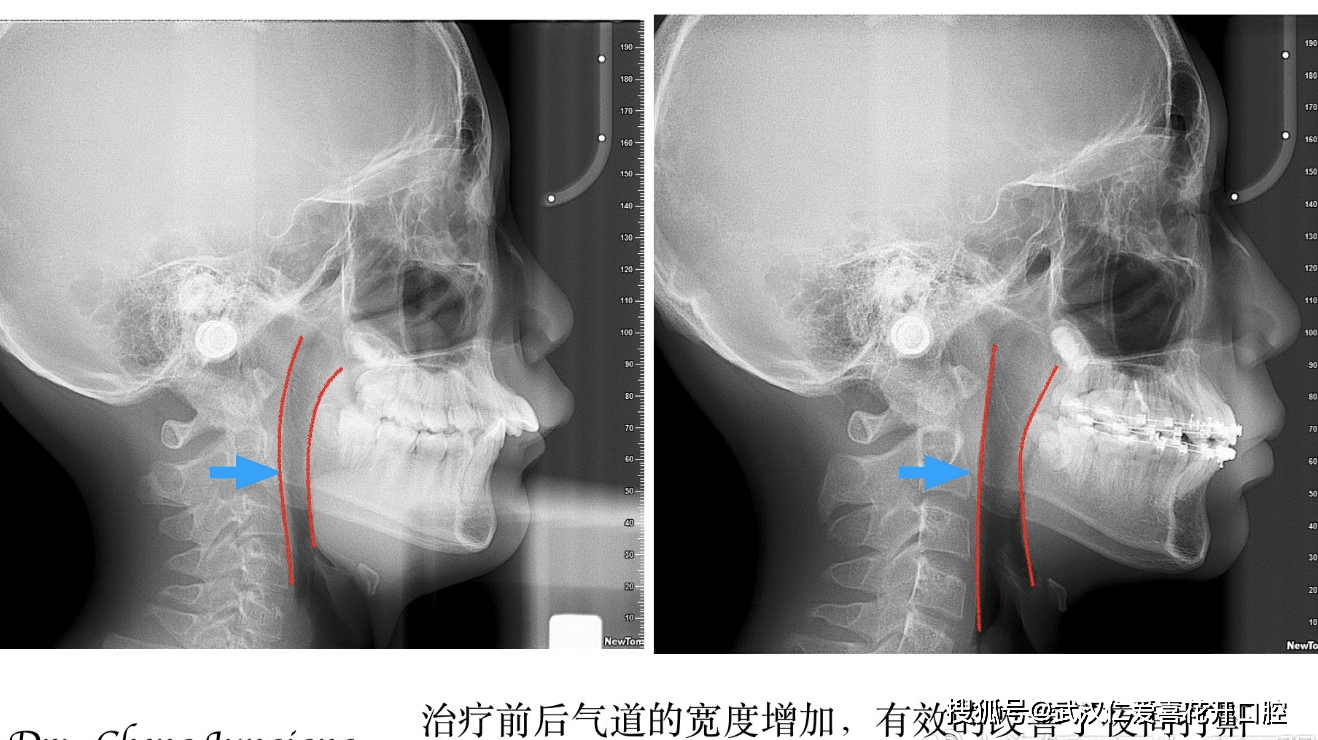

x片可见,下颌体形态长方形,气道狭窄,生长发育高峰期,双侧下颌升支长度不一致,下颌后牙代偿性近中倾斜

治疗后的侧位片

治疗后的x片可以看到牙根基本平行,面型改善,气道变宽。